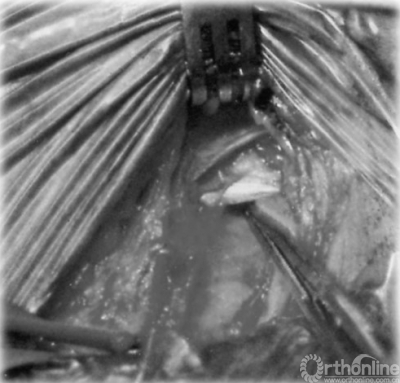

神经松解手术

对于绝大部分的脊柱后路术后出现的MP,其常常是自限性的,保守治疗被证明在超过90%的LFCN受压的MP患者都可以减轻症状,并不需要特殊的治疗。对于那些可能合并严重疼痛,感觉异常,烧灼感的患者,采取药物,理疗,局部类固醇或麻醉药物注射能够缓解其症状。最后,需要进行神经松解减压手术治疗的患者微乎其微。对于MP的恢复时间,大部分文献报道平均完全恢复时间为2周左右,一般在3个月内均能获得缓解。